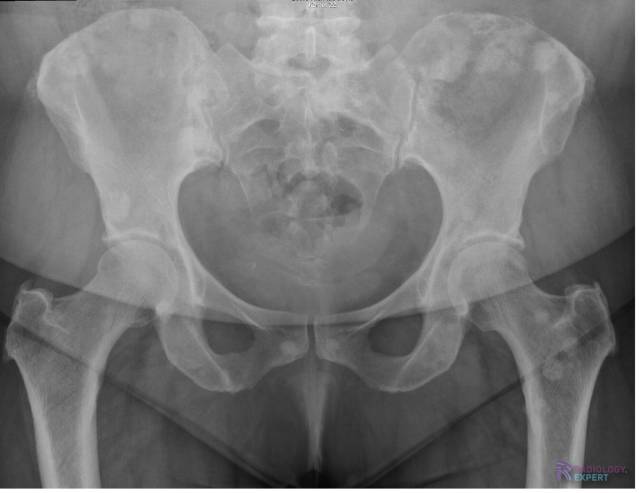

Figuur. 24. Multipele sclerotische (= blastische) laesies verspreid door het bekken en linker heup passend bij ossale metastasen. Betreft een 65 jarige patiënte met bekend ossaal gemetastaseerd mammacarcinoom.

Multipele sclerotische (= blastische) laesies bij ossaal gemetastaseerd mammacarcinoom. Multipele sclerotische (= blastische) laesies bij ossaal gemetastaseerd mammacarcinoom.